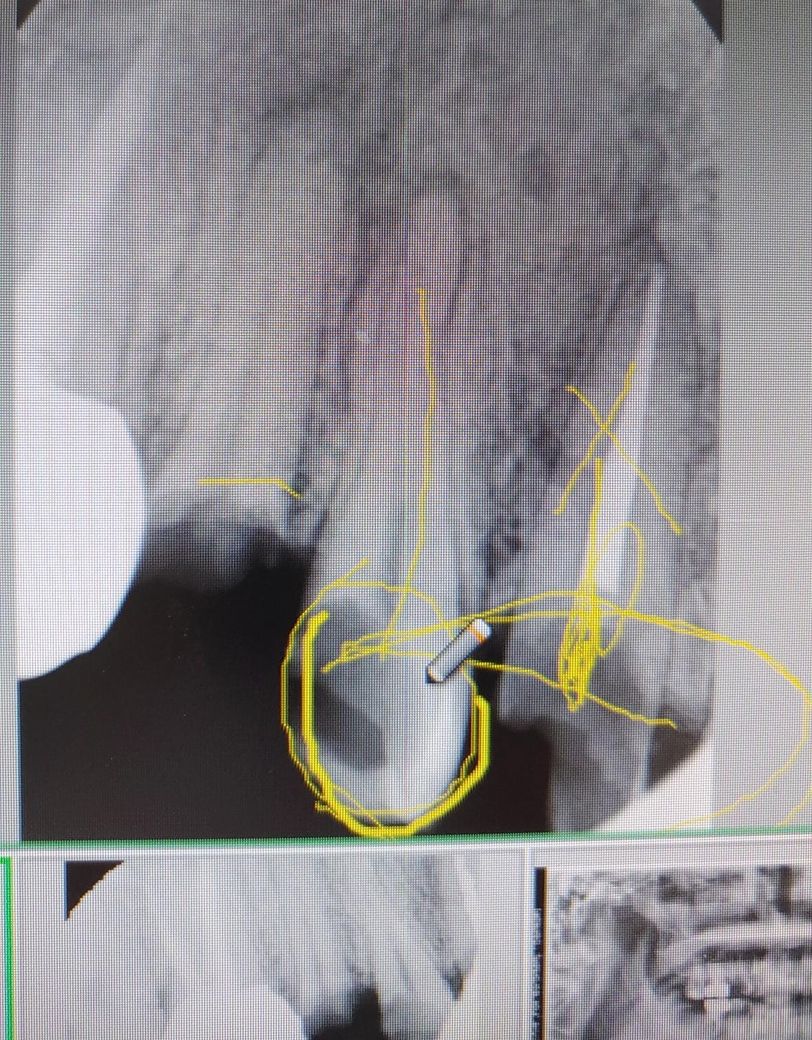

오른쪽 위 제일 작은 어금니가 충치로 치성상악동염을 일으킬 수 도있을까요?

제가 오른쪽만 상악동염에 걸렸는데 혹시 사진상에 동그라미 친 오른쪽 윗 제일 작은 어금니 때문일 가능성이 있을수도있는지 문의드립니더.

사진상으로 봤을때 해당 작은 어금니는 상악동에 영향을 주었을 확률은 높지 않아 보입니다.

치성 상악동이 생기기 위해서는 치근단 부위에 큰 병소가 있어야 되며 측은 단 끝에서 기시하는 병소가 눈에 보이는 경우가 많습니다.

사진으로 보이는 치아는 사람들이 사진상으로 보았을 경우 치아 뿌리 쪽에 치조골이 잘 형성되어 있는 것으로 보여 지성 상악동을 일으킬 가능성은 매우 낮습니다.

해당 치아의 상태는 매우 안좋기 때문에 치료를 받으셔야 하지만 상악동염의 원인으로 보이진 않습니다.

치근단 염증이 상악동 염까지 진행되는경우는 흔치 않습니다. 대부분 상악동염은 축농증이나 비염등에 의해서 생기게됩니다.